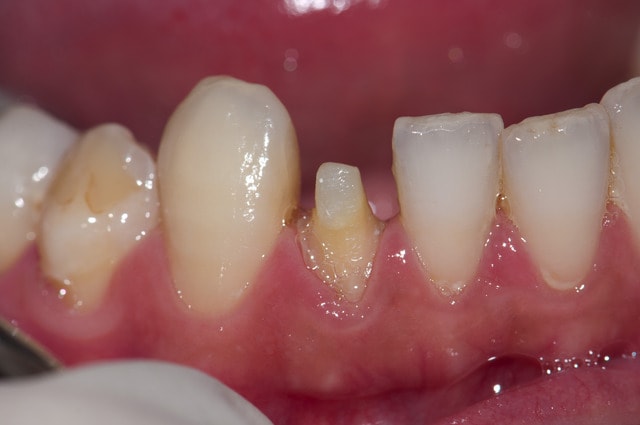

voila quelques traitements,modestes mais je suis encore jeune....

encore des radios,peut-etre assez moyen comme traitement...mais je vu pire...

Eh ben .... y a pas mal de dentiste francais qui vont rougir en voyant tes traitements

Cher confrère roumain , tu as sans doute remarqué que lorsque tu réalises de superbes endos sur molaires ( félicitations au vue des radios) tu es rémunéré généreusement par ton patient un peu plus de 80 euros le traitement complet .

Tu n'as pas besoin de moi pour te défendre; tes traitements parlent d'eux-mêmes.